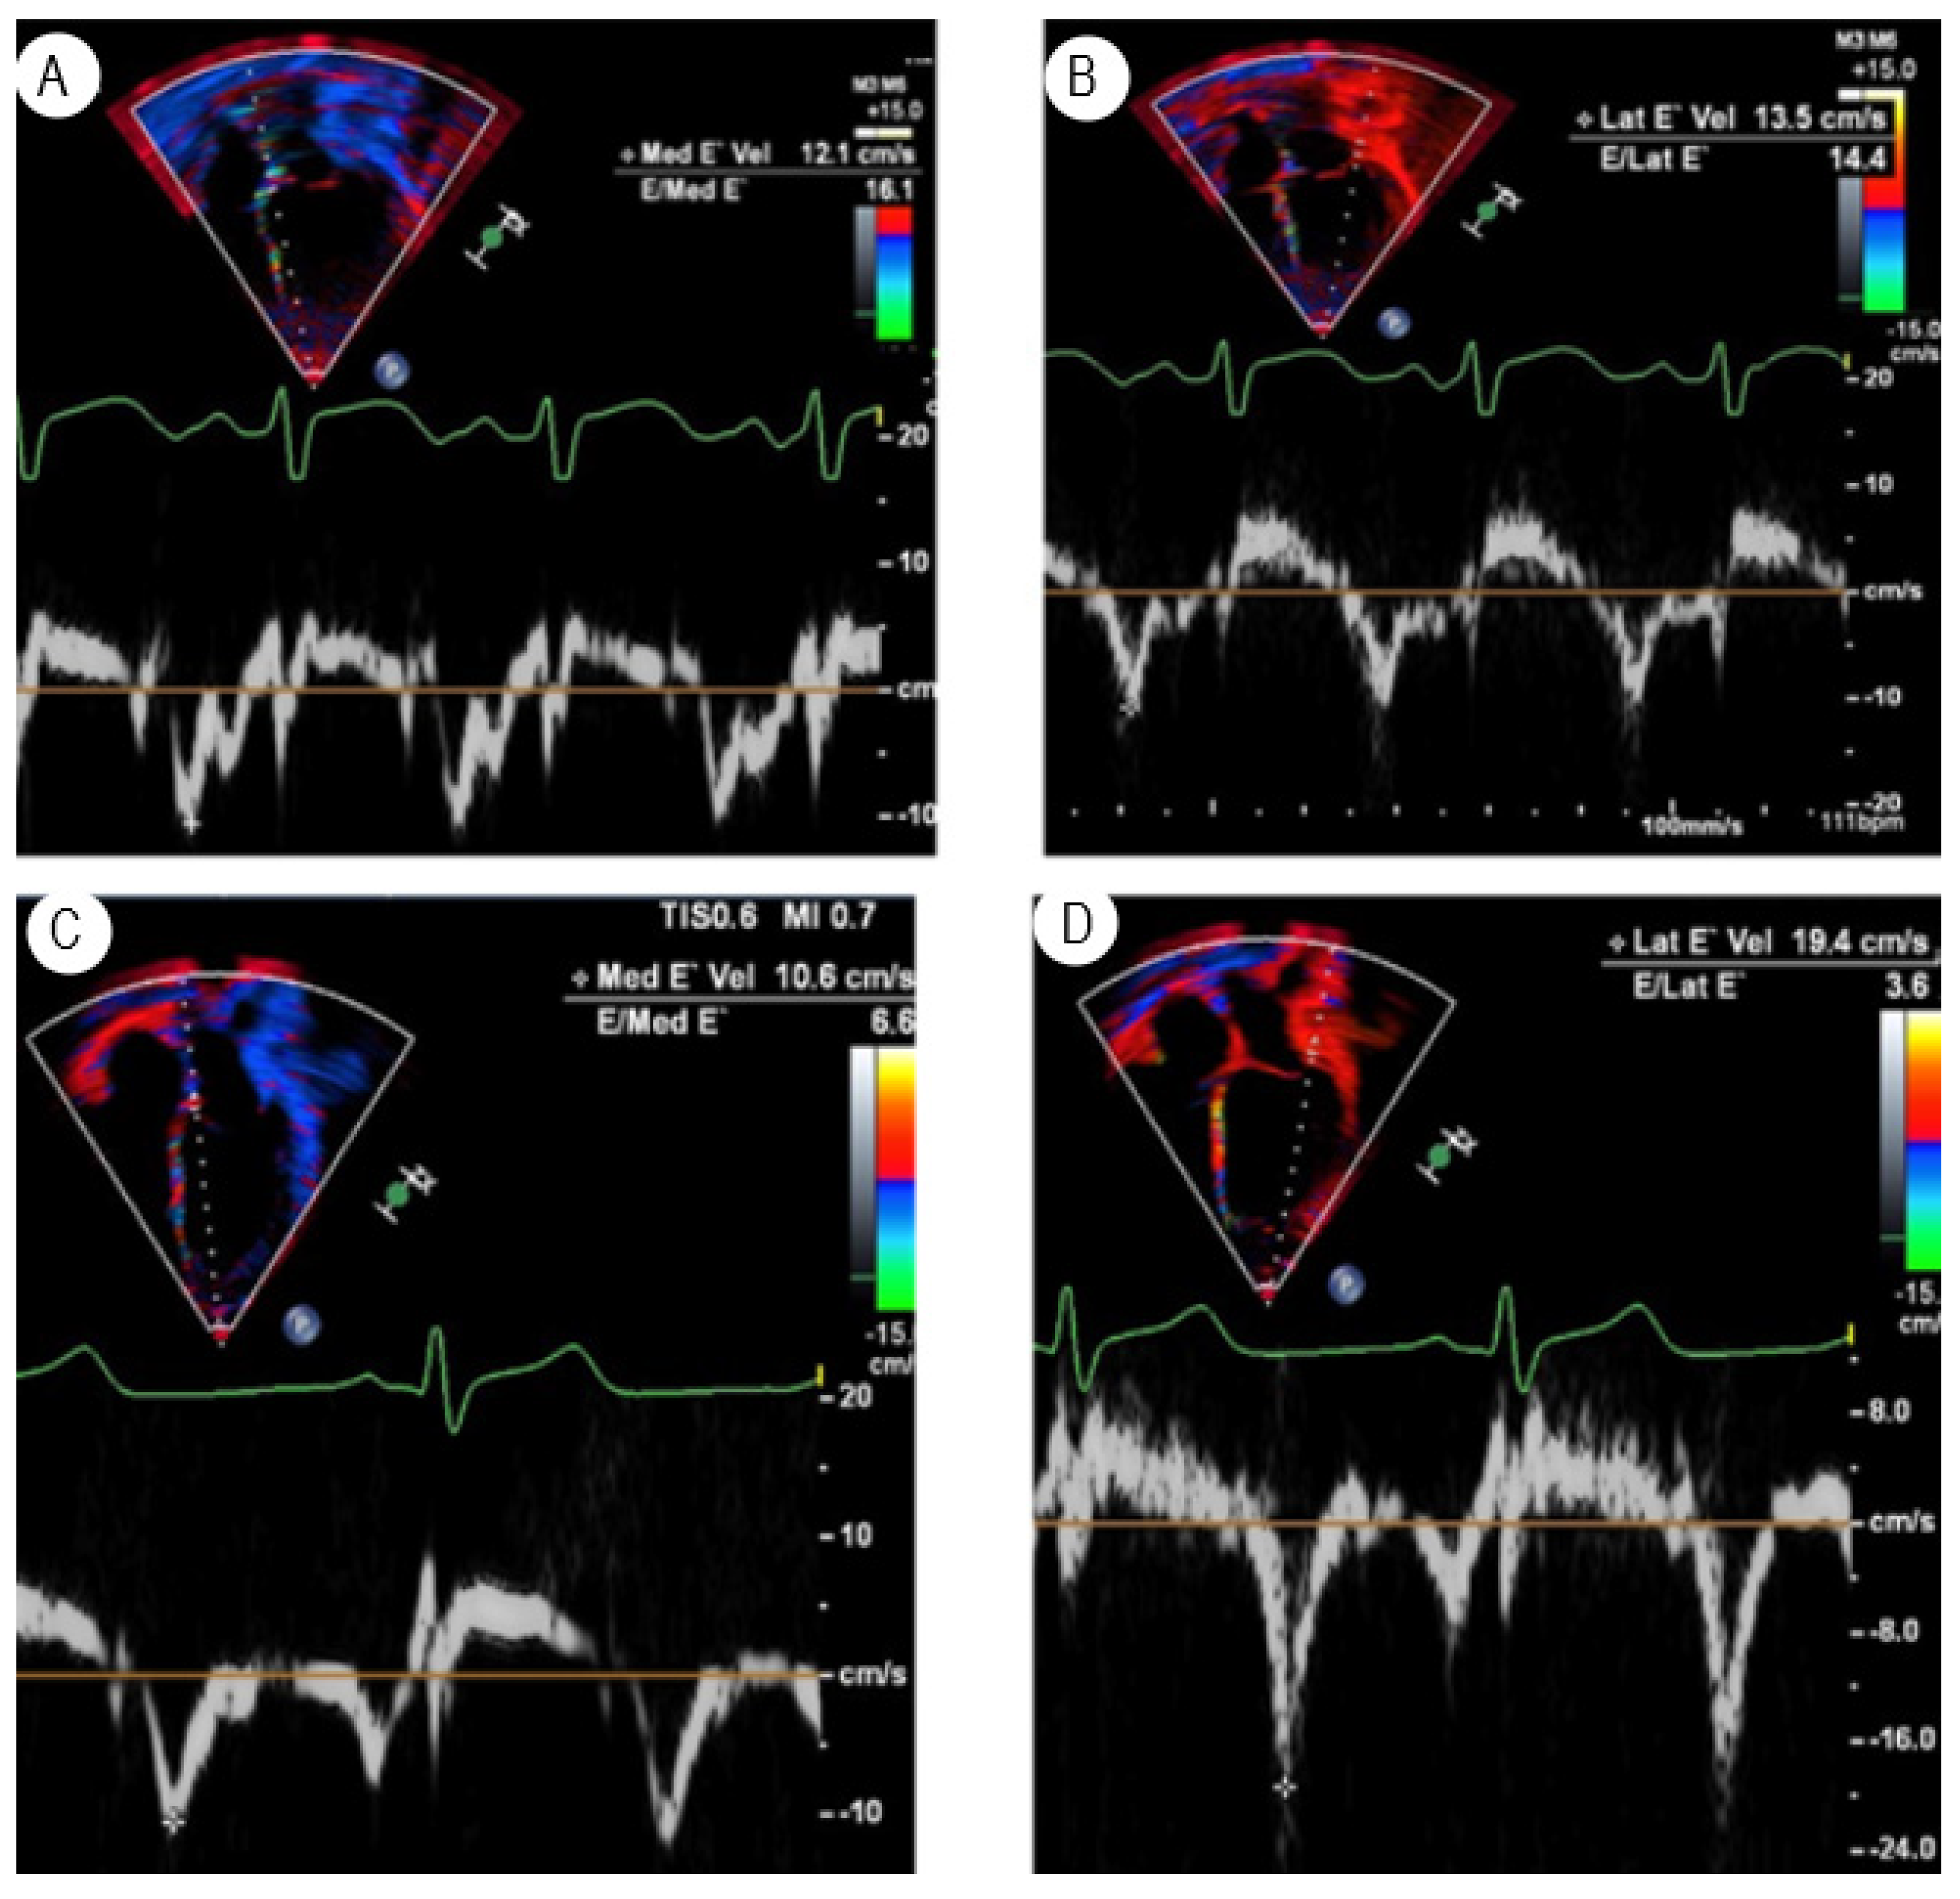

TDI-based myocardial deformation imaging can evaluate LV stiffness and diastolic dysfunction [8,12,13,14]. Both LV myocardial stiffness and diastolic dysfunction in HT recipients are likely due to low-grade subclinical rejection or coronary microvascular diseases. TDI can determine the LV diastolic function by evaluating the longitudinal movement at the mitral, tricuspid, and septal annulus levels, calculating early and late diastolic velocities (E and e’, respectively), and comparing these with reference values for children [15]. Mitral and tricuspid valve e’ < 5.0 m/s had 93% negative predictive value for rejection [16]. Another study showed that TDI at medial mitral annulus E/e’ > 12 is associated with elevated left ventricular end-diastolic pressure (LVEDP) and high-grade cellular rejection, and a lateral tricuspid annulus E/e’ > 10 is associated with elevated mean right atrial pressure [17]. However, the role of TDI is controversial in pediatric HT recipients and has resulted in mixed results, as one study demonstrated no correlation with LVEDP [18]. Yet another study showed that EMB-proven rejection is associated with a significant decline in biventricular TDI velocities from baseline [19]. By using well-defined TDI criteria to predict non-rejection, a substantial proportion of planned biopsies can be deferred or avoided in pediatric HT recipients. In addition, many recent studies suggested that TDI parameters help discriminate rejection from non-rejection and can be used as noninvasive surveillance alternatives to EMB [16,20,21]. An example of abnormal LV myocardial velocities in pediatric HT recipients with confirmed rejection by EMB (Grade 2R acute cellular rejection) and normal TDI in another HT of the same age patient are shown in Figure 2A–D, respectively. The disadvantages of TDI in children include variable results with different vendors and the absence of normal reference values established for pediatric HT recipients. The advantage of TDI includes higher temporal resolution and less image dependence.

Figure 2. (A) TDI of the medial mitral annulus and (B) lateral annulus of the mitral valve in a six-year-old female three months post-transplant, showing diastolic dysfunction. E/e’ at medial mitral annulus 16.1 and at lateral annulus 14.4. (C,D) show the normal TDI at the medial and lateral annulus of the mitral valve in another 6-yr-old HT recipient who is doing well.